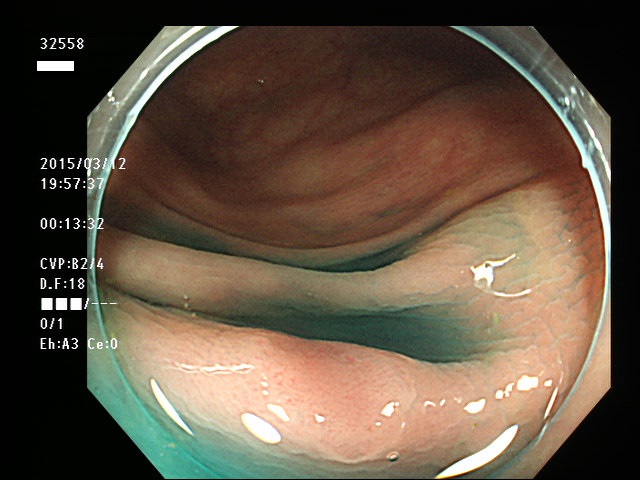

上記100名より抽出した平坦・陥凹型腺腫(=癌化の危険が高いが見落としやすい病変)の内視鏡写真

32550 32553 32555 32556 32558 32559 32560 32562 32563 32564 32568 32569